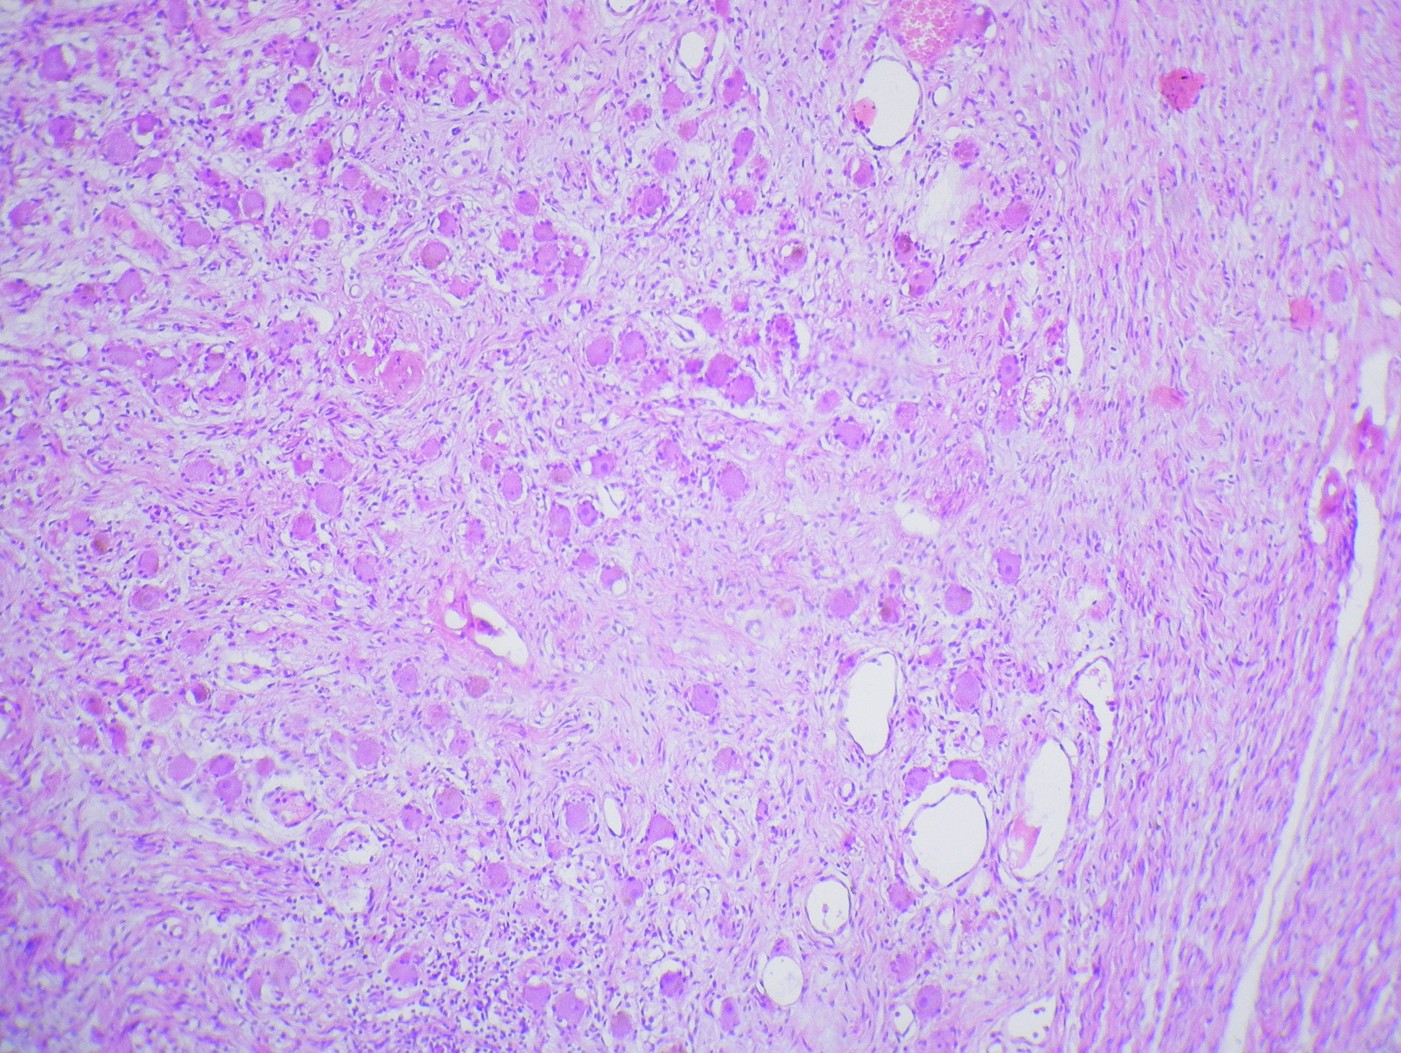

The usual challenge in examing body cavity fluids (pleural fluid, peritoneal fluid) is to distinguish benign from malignant cells. This tak...